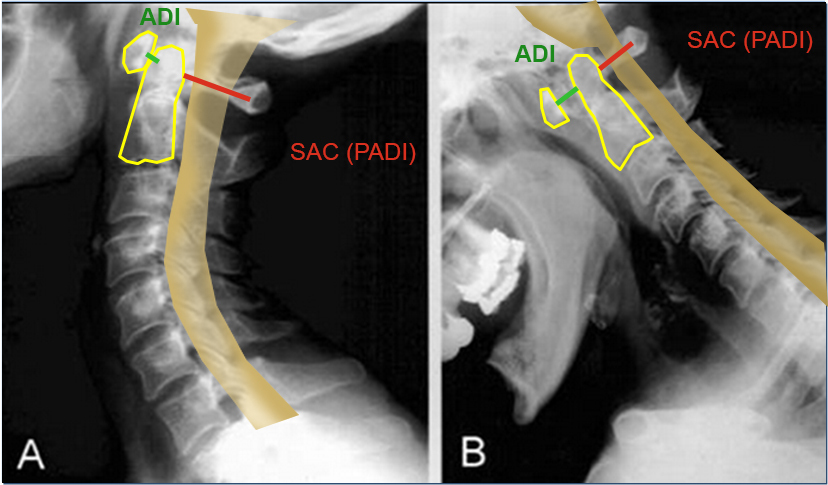

PADI>14mm

Boden and associates’ article presents compelling evidence that patients with rheumatoid arthritis and neurologic deterioration in C1-2 instability are more likely to achieve some improvement if the posterior atlanto-dens interval is greater than 10 mm on preoperative studies. All the patients in their series who had neurologic deterioration and a preoperative posterior atlanto-dens interval of greater than 14 mm achieved complete motor recovery.

Boden et al. “The most important predictor of the potential for neurological recovery after the operation was the preoperative posterior atlanto-odontoid interval (PADI). In patients who had paralysis due to atlanto-axial subluxation, no recovery occurred if the PADI was less than 10mm, whereas recovery of at least one neurological class always occurred when the PADI was at least 10mm. All patients who had paralysis and a PADI or diameter of the subaxial canal of 14mm had complete motor recovery after the operation.” They found no correlation with the anterior atlanto-odontoid interval (ADI) with the severity of paralysis or the potential for recovery.

Xrays to determine AADI and PADI:

- 3.5 mm on flex/ex

- PADI <14 mm more sensitive than AADI measurement for spinal cord compression in patients w/ RA. More sensitive for identifying patients at risk of neuro injury.

Xrays determine mechanical instability: c1-c2 relationship.

* AADI >9-10 mm= surgery due to risk of neurologic injury

* PADI <14 mm= surgery due to risk of neurologic injury

* 3.5 mm on flexion/ext views, though radiographic instability is common in RA and not necessarily indication for surgery.

PADI <14 mm more sensitive than AADI measurement for spinal cord compression in patients w/ RA. More sensitive for identifying patients at risk of neuro injury.